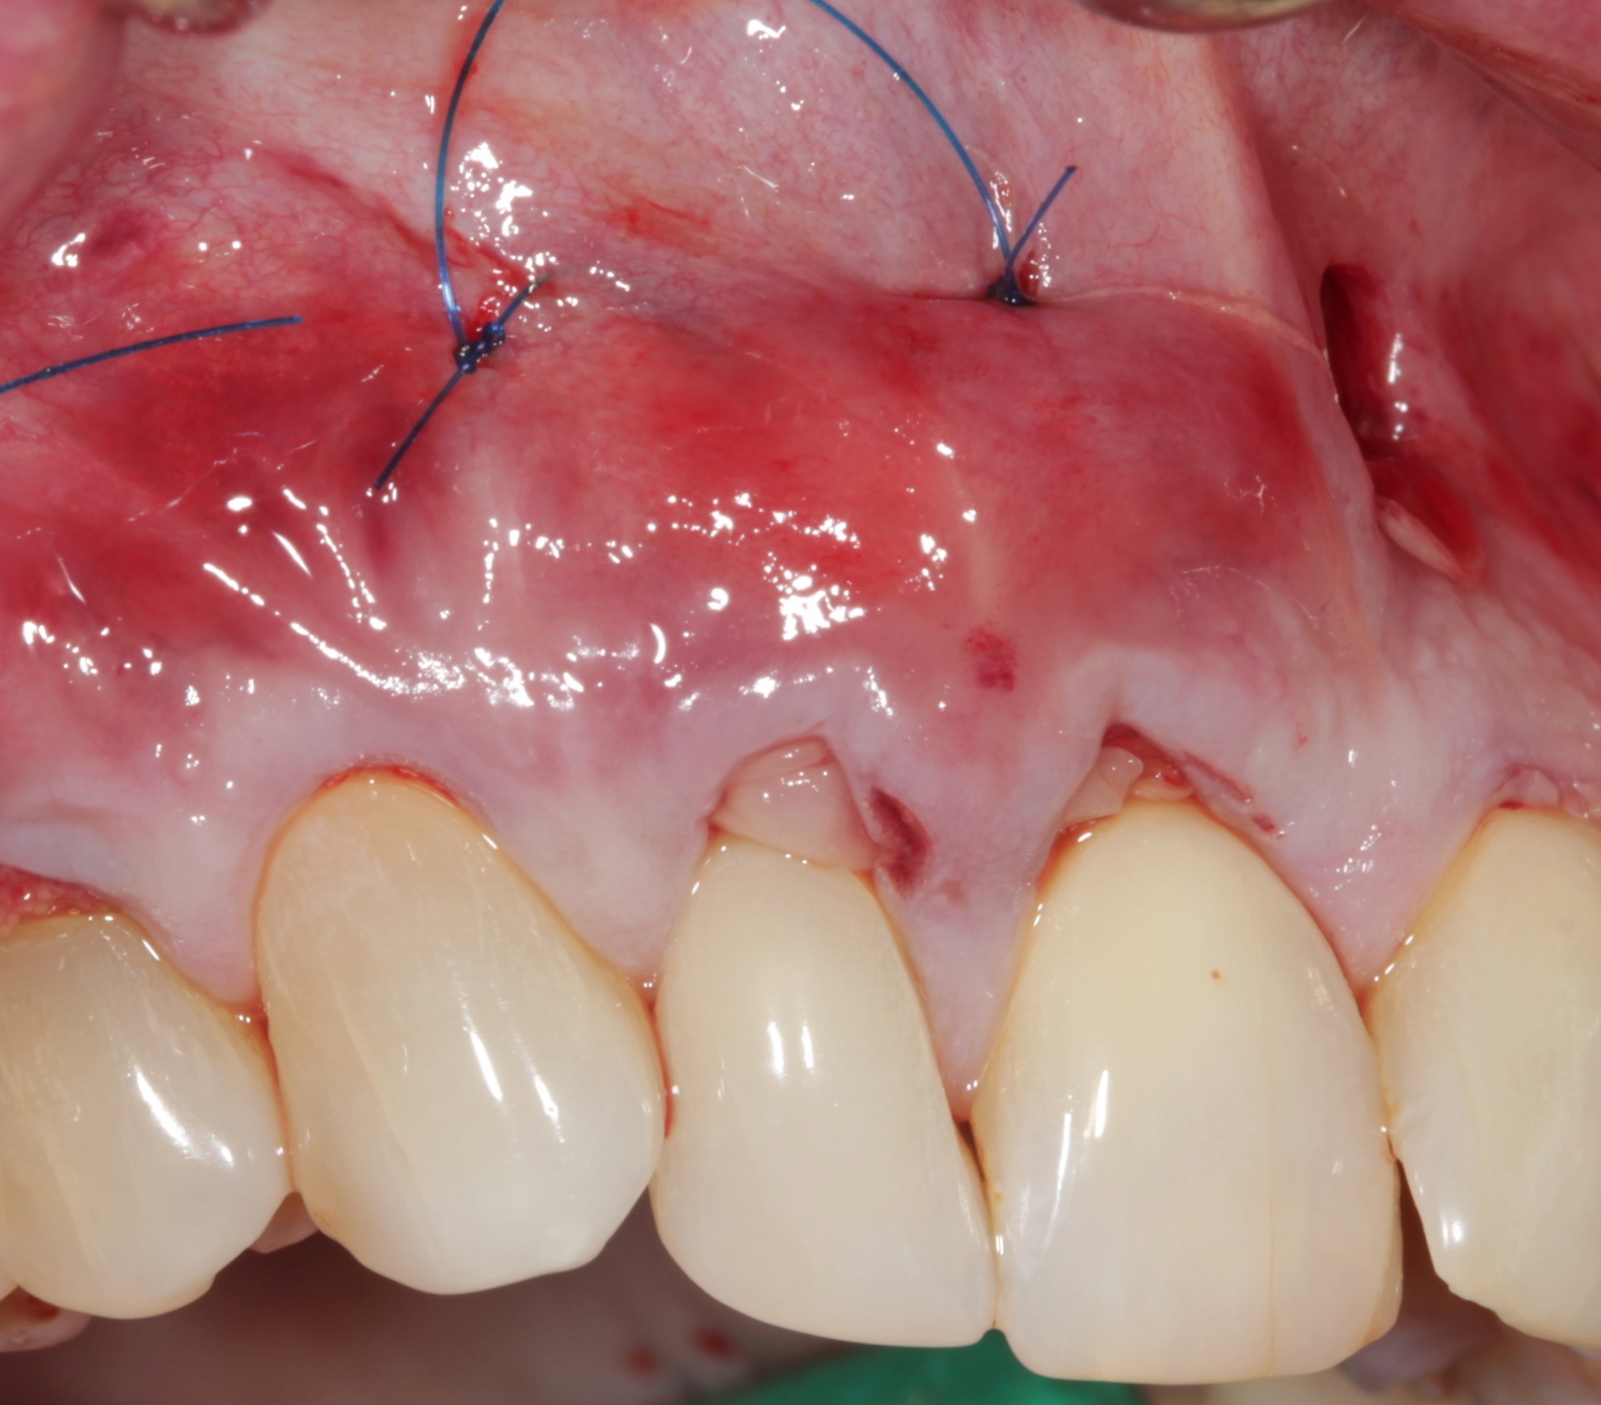

Suturing

Apical periosteal mattress sutures are the core of the suturing technique and have several purposes. The goals are to avoid marginal suture tension on the APRF membranes, stabilize and maintain the membranes on the roots’ surface, and circumvent any traveling of the membranes into the mucosal area (Figure 8).

Fig 8. Apical periosteal suture below the mucogingival junction will “lift” the APRF/flap complex coronally. This intimate proximity of the APRF membranes with the periodontal ligaments will allow for a slow release of growth factors, thus promote keratinization.

Figure 8